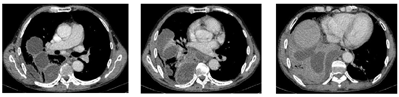

患者肺脓肿并多房包裹性脓胸诊断明确。于11月3日在CT引导下行包裹性脓胸穿刺(图7)及置管引流(图8)术。穿刺处胸水常规:深黄色、微浊胸水,无凝块,白细胞总数29×106/L,单个核细胞31%,多个核细胞69%,红细胞0×109/L,李凡他实验+;胸水生化:白蛋白25.5 g/L,球蛋白17.7 g/L,总蛋白43.2 g/L,淀粉酶40 U/L,葡萄糖7.01 mmol/L,乳酸脱氢酶556 U/L,腺苷脱氨酶17.91 U/L。胸水检验结果支持肺炎旁胸腔积液。置管处胸水常规:黄色、浑浊胸水,无凝块,白细胞总数100803×106/L,单个核细胞15%,多个核细胞85%,红细胞38×109/L,李凡他实验+++;胸水生化:白蛋白26.4 g/L,球蛋白23.6 g/L,总蛋白50 g/L,淀粉酶30 U/L,葡萄糖0.03 mmol/L,乳酸脱氢酶7020 U/L,腺苷脱氨酶130.15 U/L;胸水培养(需氧菌+厌氧菌)阴性;未查见抗酸杆菌。引流出脓性胸水约200ml(图9)。胸水检验结果支持脓胸。复查红细胞沉降率102 mm/h;血常规:白细胞计数11.9×109/L,中性粒细胞绝对值9.15×109/L,血红蛋白103 g/L,中性粒细胞百分率76.9%;C反应蛋白260.45 mg/L;肝功能:白蛋白33.5 g/L,直接胆红素26.2 umol/L,总胆红素32.4 umol/L,总胆汁酸17 umol/L;降钙素原0.69 ng/ml。予生理盐水和碳酸氢钠反复冲洗脓腔、尿激酶(1万U,1次/d)胸腔内注射,同时给予人血白蛋白静脉滴注以纠正低蛋白血症。复查胸部彩超提示右侧胸腔包裹性积液,积液黏稠,周围壁及分隔较厚。复查胸部CT(图10、图11)示:右肺上叶后段、右肺中叶及下叶多发感染并右肺下叶肺脓肿形成,右肺感染较前有所吸收;右侧胸腔引流术后,右侧胸腔积液、积脓较前吸收减少;右侧胸膜增厚。于11月8日再次在CT引导下行包裹性脓胸穿刺术。患者临床症状逐渐改善,11月17日复查红细胞沉降率96 mm/h;血常规:白细胞计数7.89 ×109/L,中性粒细胞绝对值4.53×109/L,血红蛋白104 g/L,中性粒细胞百分率57.4%;C反应蛋白25.75 mg/L;白蛋白40.8 g/L;降钙素原正常。11月22日复查胸部CT(图12,图13):右肺下叶见片状、不规则状密度增高影,部分可见液化坏死,较前片吸收好转;右肺底局限性包裹性积液;双肺下叶、右肺中叶感染;右侧胸膜弥漫性增厚,右侧胸腔包裹性积液;右侧斜裂少许包裹性积液;纵隔淋巴结肿大。11月23日复查红细胞沉降率60 mm/h;血常规:白细胞计数5.57×109/L,中性粒细胞绝对值2.76×109/L,血红蛋白106 g/L,中性粒细胞百分率49.6%;C反应蛋白11.93 mg/L;电解质正常。患者病情好转于11月24日出院,继续口服莫西沙星和甲硝唑抗感染治疗1个月。